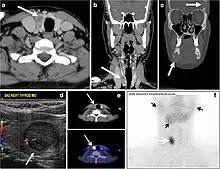

Fig. 9. A 58-year-old male patient with persistence PTC at thyroid bed with hypervascular nodal metastasis. a–c Transverse greyscale and colour Doppler neck ultrasound demonstrate hypoehoic soft tissue in the left thyroid bed (white arrow in a). There are a heterogeneous enlarged lymph nodes at level 2 and 3 with markedly increased vascularity (white arrow in b and c). d–f Enhanced axial CT images of the neck demonstrate a 2.7 × 1.4 cm hypodense soft tissue lesion anterior to the left carotid sheath (white arrow). There are left-sided enhancing abnormal and enlarged lymph nodes at cervical level 2 and 3 (black arrows).[1]

Fig. 11. Thyroid non-Hodgkin's large B-cell lymphoma in a 66-year-old female patient. an Axial enhanced neck CT scan demonstrates left thyroid lobe and isthmus homogeneously hypodense and minimally enhancing mass (white arrows). This lesion invades the prevertebral muscles (black arrows). Note the multiple enlarged level V lymph nodes (white arrowheads). b Post-treatment image shows significant reduction in size and mass effect of the left thyroid infiltrative mass, with almost complete resolution of the left cervical lymphadenopathy.[1]

Fig. 12. Diffuse thyroid large B-cell lymphoma in a 79-year-old female patient. an Axial enhanced neck CT scan demonstrates a homogeneously hypodense and minimally enhancing large right thyroid solid mass (long white arrow) extending into the thyroid isthmus. It is encasing the right carotid artery (short white arrow) and displacing of the trachea and oesophagus to the left side.[1]